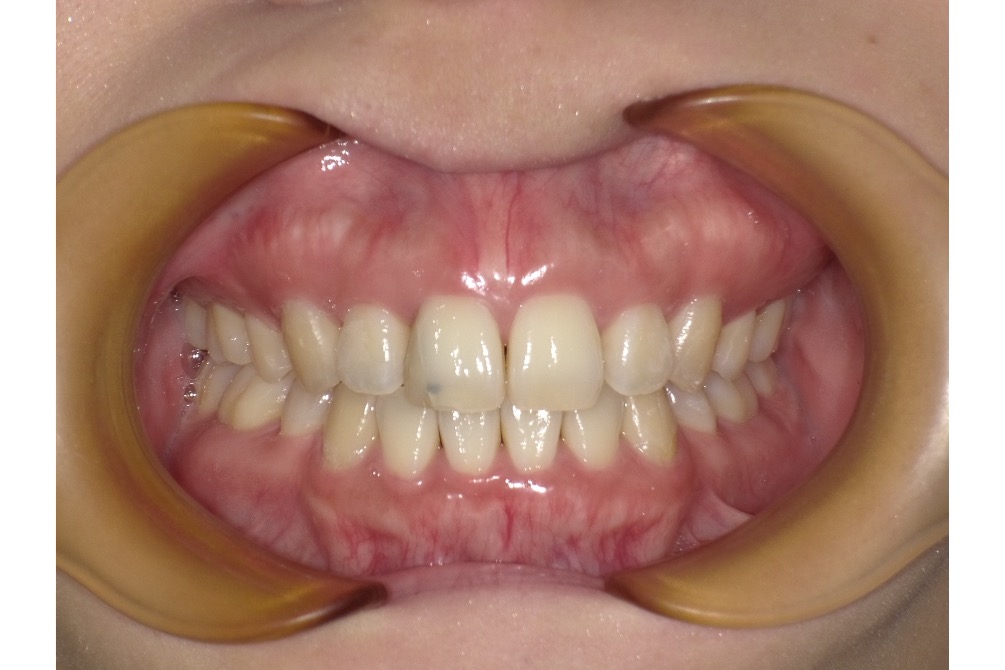

■ 1. 「歯茎が薄い人」とはどんな状態?

歯茎の厚みは人によって大きく違い、

厚みがあるタイプ/薄いタイプに分かれます。

歯茎が薄い人は、以下の特徴がみられやすいです。

- 歯の根元が透けるように見える

- 歯と歯茎の境目がシャープ

- 歯茎がピンクではなく明るい色

- ブラッシングで出血しやすい

- 歯の表面が少し長く見える傾向

歯茎は“歯の根元を守るクッション”のような役割を持っています。

薄いと、そのクッションが弱いため、矯正で歯が動くときの負担に弱いことがあるのです。